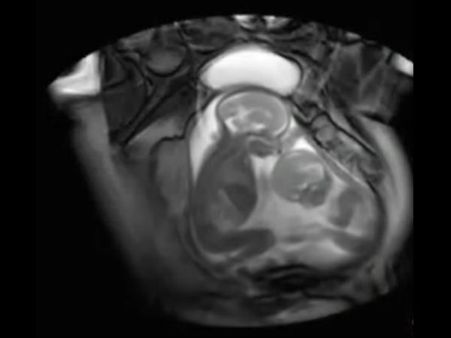

Here's another example to show a similar case such as this, where non-identical twins were born to a woman sharing the DNA of two different fathers!

Image SourceDo share your thoughts and comments on this in the comment section below.